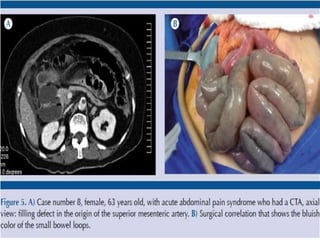

63-year-old woman status post aortic valve replacement who presents with a one

63-year-old woman statuspost aortic valve replacement who presents with a one week history of abdominal pain becoming quite severe over the last 24 hours.